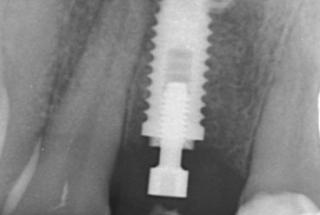

Clinical cases

MPI closely monitors clinical cases in the market to ensure their correct functioning and successful outcome.